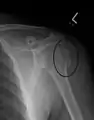

Diagnosis

Definitive diagnosis of humerus fractures is typically made through radiographic imaging. For proximal fractures, X-rays can be taken from a scapular anteroposterior (AP) view, which takes an image of the front of the shoulder region from an angle, a scapular Y view, which takes an image of the back of the shoulder region from an angle, and an axillar lateral view, which has the patient lie on his or her back, lift the bottom half of the arm up to the side, and have an image taken of the axilla region underneath the shoulder.[9] Fractures of the humerus shaft are usually correctly identified with radiographic images taken from the AP and lateral viewpoints.[12] Damage to the radial nerve from a shaft fracture can be identified by an inability to bend the hand backwards or by decreased sensation in the back of the hand.[5] Images of the distal region are often of poor quality due to the patient being unable to extend the elbow because of pain. If a severe distal fracture is suspected, then a computed tomography (CT) scan can provide greater detail of the fracture. Nondisplaced distal fractures may not be directly visible; they may only be visible due to fat being displaced because of internal bleeding in the elbow.[7]